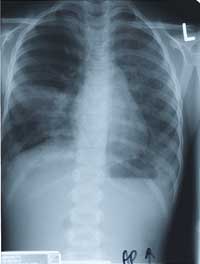

BELOW, CHEST X-RAY from October 1998.

Enlarge the CHEST X-RAY LEFT, enlarge the chest x-ray RIGHT.

WHAT ARE YOUR FINDINGS. WHAT WOULD YOU DO NEXT?